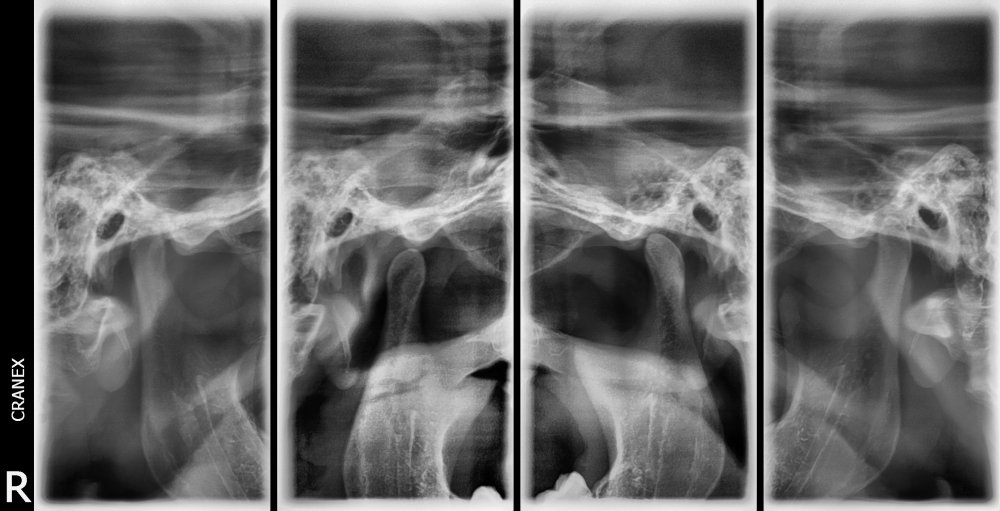

- RX .A.T.M (Boca cerrada / Boca abierta )